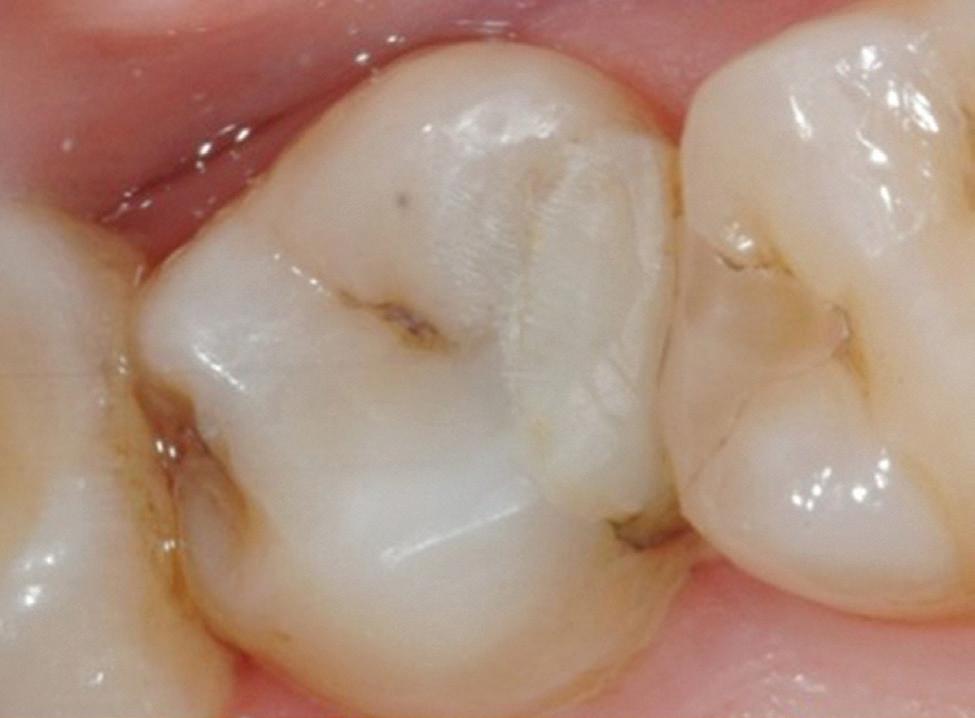

With the increasing use of all ceramics within practice, a clinician must under stand adhesive procedures to ensure adequate bond strength for predictability and longevity. Clearfil ceramic primer plus is a single com ponent adhesive primer used to enhance bond strength between resin-based materials, as well as porcelain, composite, hybrid ceramics, metal oxide (zirconia) and lithium disilicate. It contains the adhesive phosphate containing monomer (MDP) used for adhesive bonding as well as to metal oxide. Additionally, it contains a silane cou pling agent which guarantees strong adhesion to all glass-based ceramic materials. It is a one bottle system meaning there is no mixing and has excellent shelf life compared to other silanes which need to have careful storage.

Estelite Asteria (Tokuyama)One of my favourite composite resin materials is Asteria which is a light-cured radiopaque composite for universal use. It considerably simplifies multilayer techniques yet delivers outstanding aesthetics with excellent polishability. Unlike mul tilayer techniques used with conventional composites, Asteria uses only 2 layers for optimal results without compromising aesthetics. The microstructure of the material produces a light diffusion that helps blend in with the natural tooth structure. The chameleon like nature of the material allows a blending of the materials to natural tooth structure and it allows excellent polishability which retains its lustre over time.